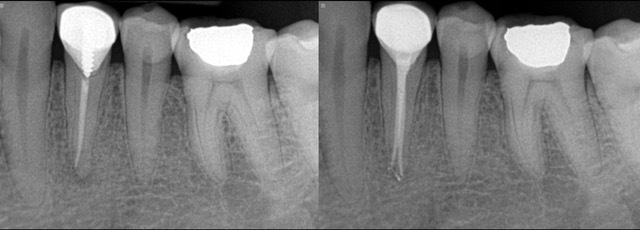

- X-ray findings: Regular dental checkups include X-rays to monitor any changes in your teeth and roots over time. These images can reveal signs such as new infections or persistent infection despite previous treatment.

The endodontist will start by taking X-rays to assess the condition of the tooth and determine if re-treatment is necessary. They will also administer local anesthesia to ensure your comfort throughout the procedure. Next, they will carefully remove any previous filling material and clean out the canals thoroughly. This may involve using special tools to remove stubborn bacteria or debris. Once the canals are cleaned, they will be reshaped and disinfected before being filled with a new rubber-like material called gutta-percha. The endodontist may also place a temporary filling on top for added protection.